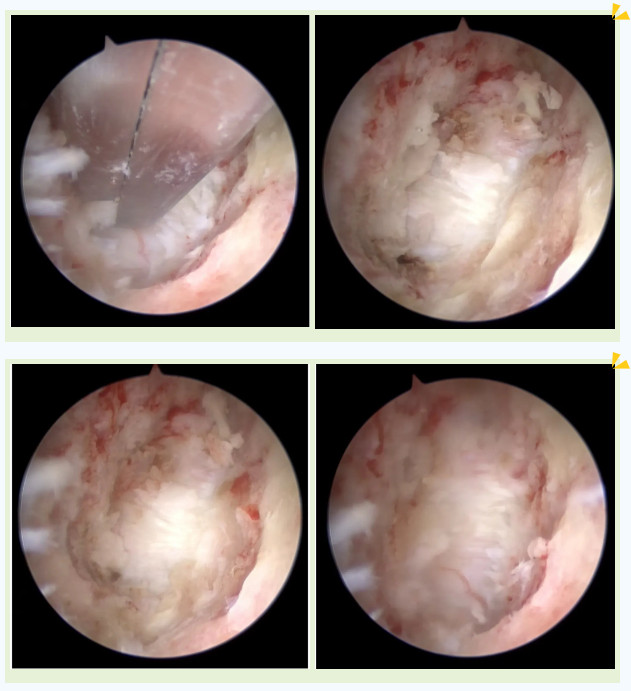

手術圖片

吳阿婆手術時的內(nèi)鏡下圖片

突破后縱韌帶后順利到達頸髓